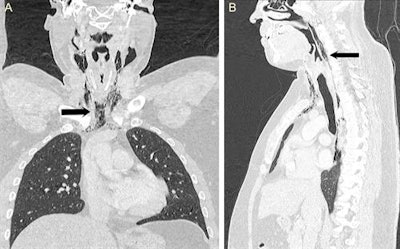

Coronal and sagittal CT scan of the neck and thorax confirmed the presence of surgical emphysema within the neck as well as pneumomediastinum extending from the skull base up to the T9 vertebra (black arrow)."CT scan of the neck and thorax with water-soluble contrast swallow should be used as the gold-standard investigation, which can confirm the diagnosis and defines the exact pathological site," they wrote. "In addition, the normal CT appearance of the lung parenchyma and esophagus helps to exclude more serious causes of pneumomediastinum such as tracheobronchial rupture and Boerhaave's syndrome."